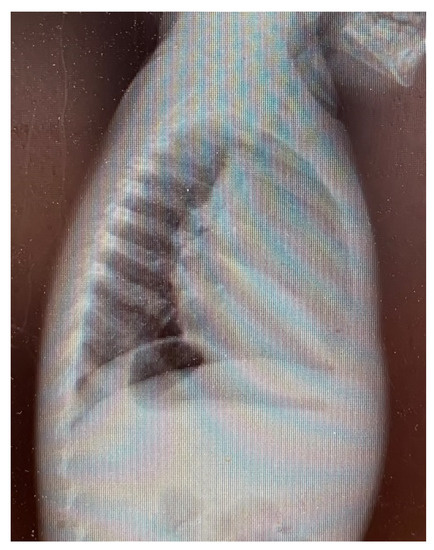

3. Results